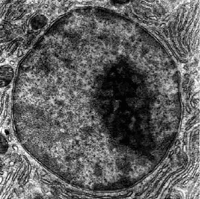

| Nucleus and Nucleolus | Two layer outer membrane with numerous pores, encloses cells DNA. | Directs all functions of Cell. Nucleolus is a collection of proteins and RNA stored for ribosome production. |

Nucleus

The Nucleus of the cell directs all the activities of the cell. It contains the cells DNA made up into various genes, and is the site of manufacture of mRNA. We will look at all this in further detail when we look at:

The membrane of the nucleus is in fact a double layer of phospholipid membrane with numerous pores. Each pore is guarded by numerous protein complexes which makes it functionally smaller than it appears on EM. Even so the pores can let through molecules of a molecular weight of up to 45,000. The interior of the cell membrane is also continuous with the endoplasmic reticulum.